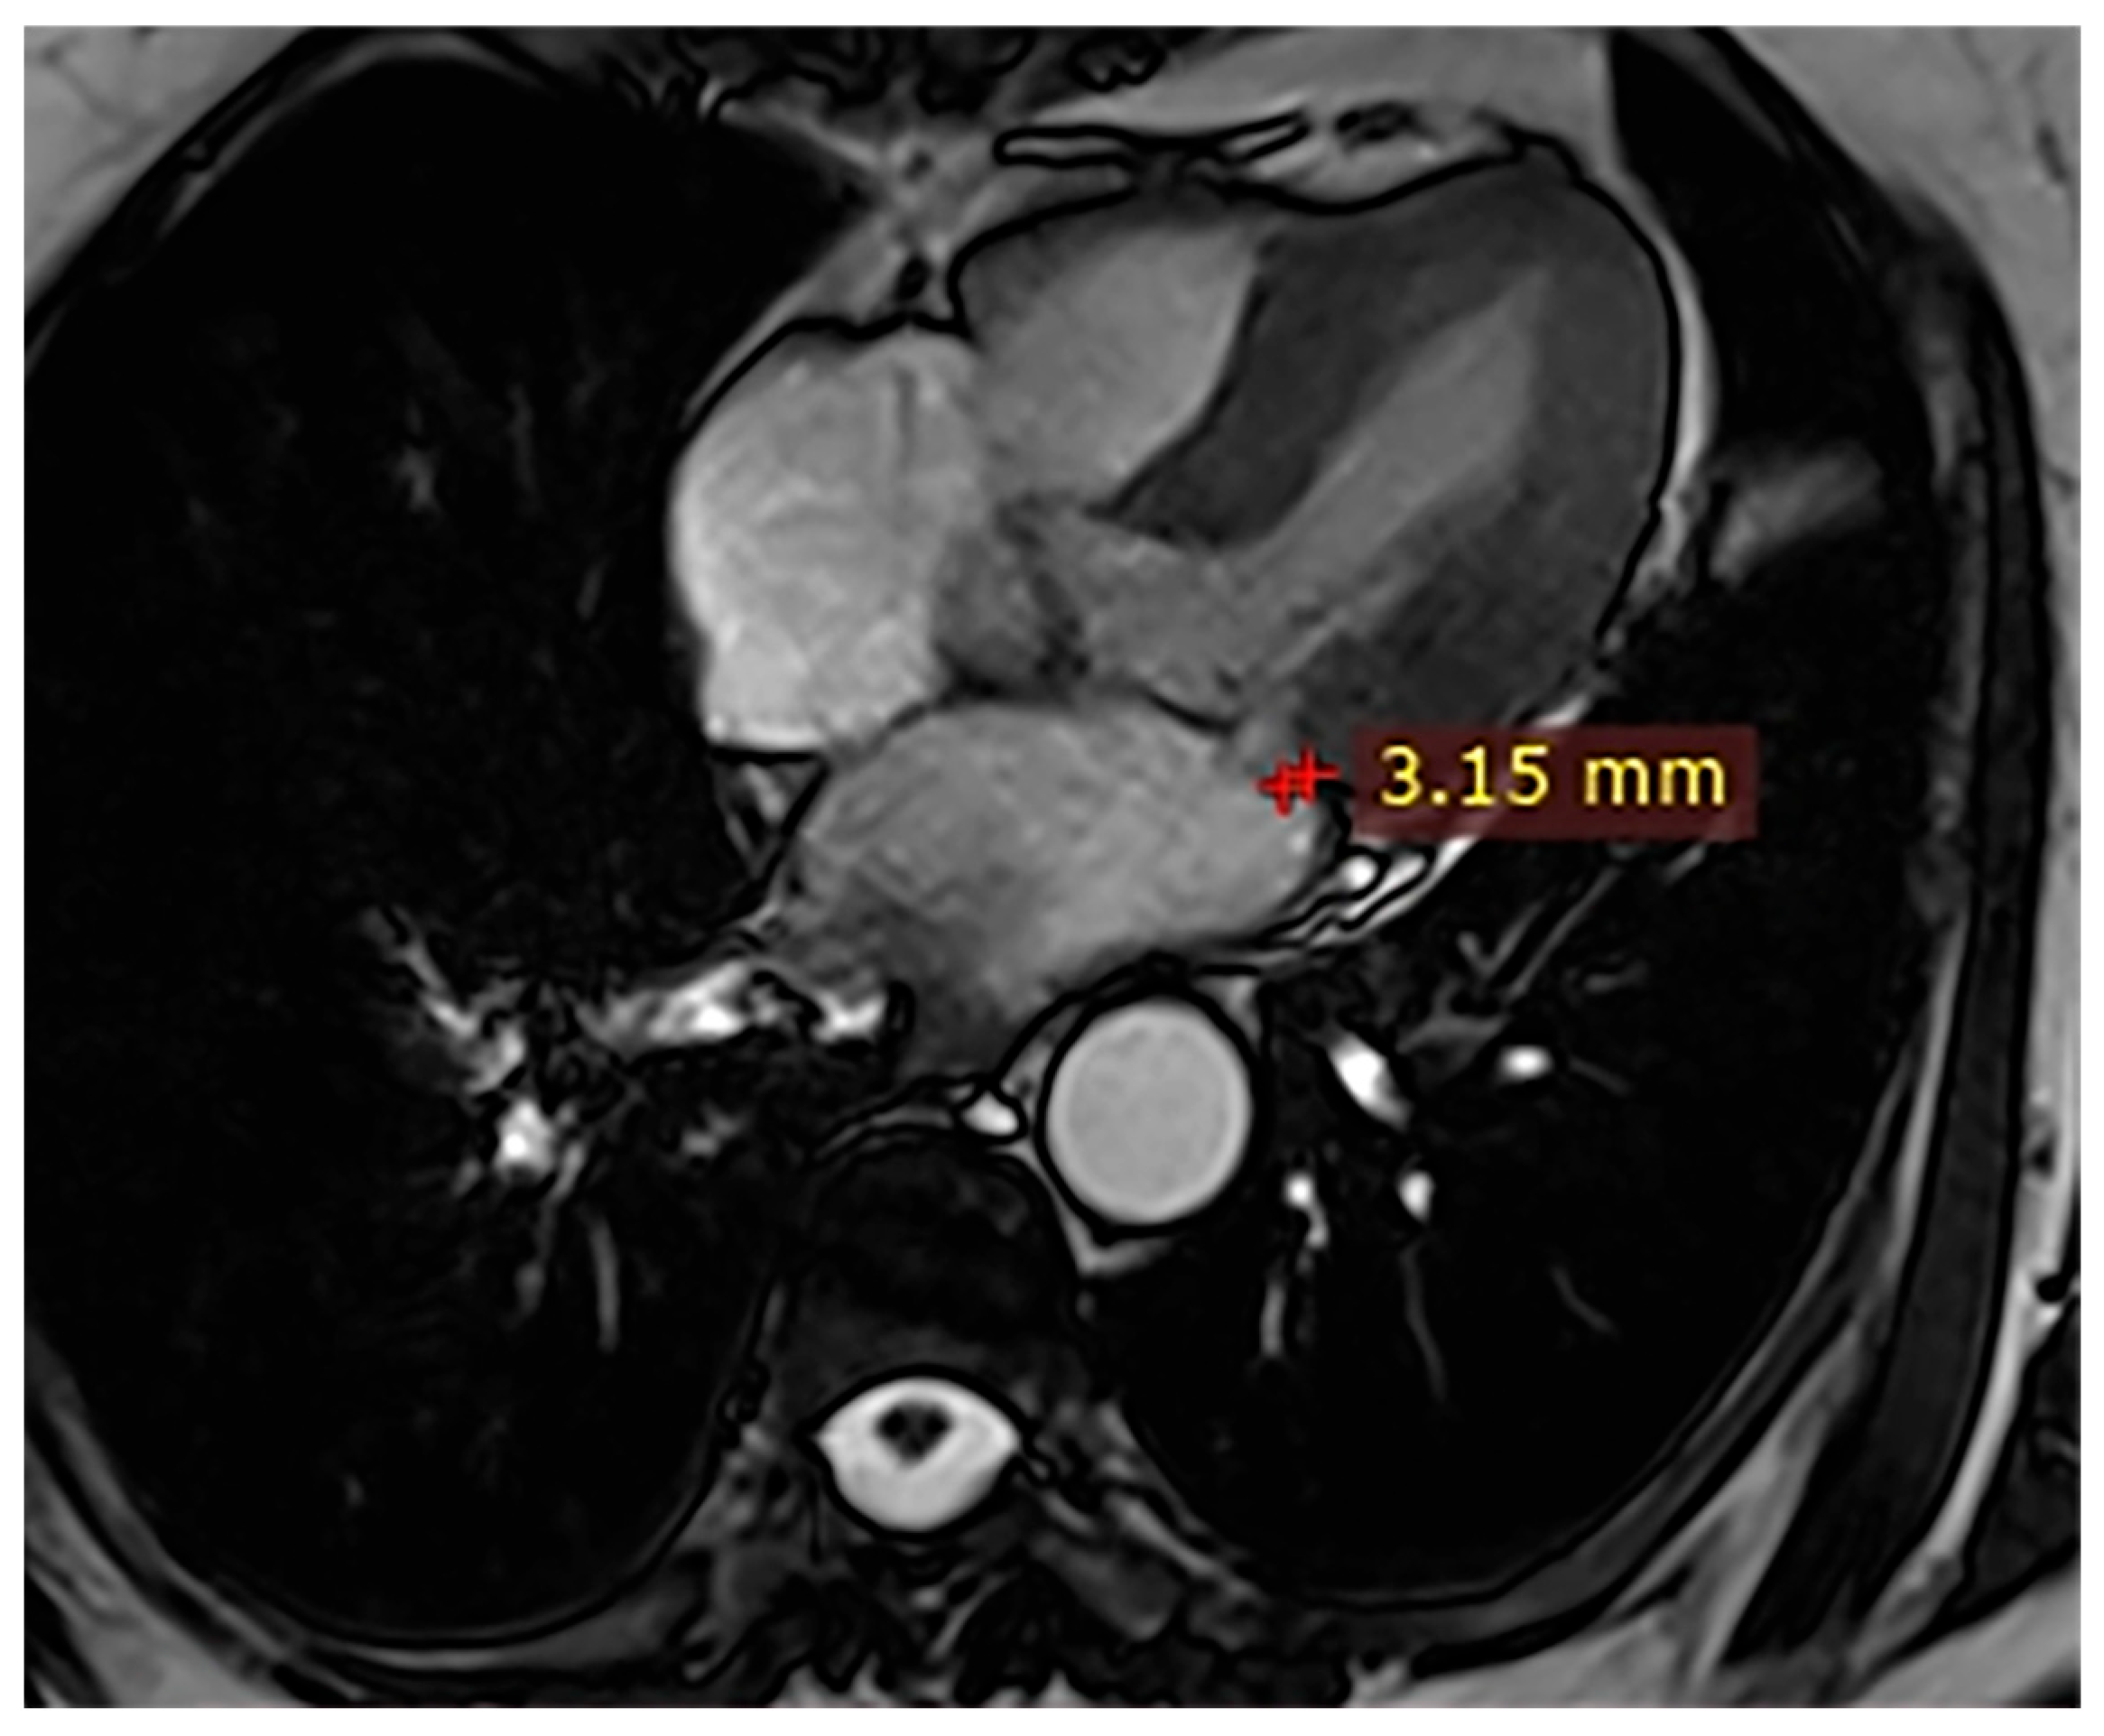

Case 4. A 34-year-old man with Marfan syndrome and premature ventricular contractions had CMR demonstrating preserved LVEF (54%), a posterior MAD of 15 mm (Figure 4), MVP with mitral regurgitation, and no LGE. Given the underlying connective tissue disease and valvular dysfunction, close cardiology monitoring was advised to evaluate progression and arrhythmic risk.

Figure 4.

Cardiac magnetic resonance (CMR), three-chamber steady-state free precession (SSFP) cine. A 15 mm mitral annular disjunction (MAD) with associated mitral valve prolapse (MVP) in a patient with Marfan syndrome is observed.